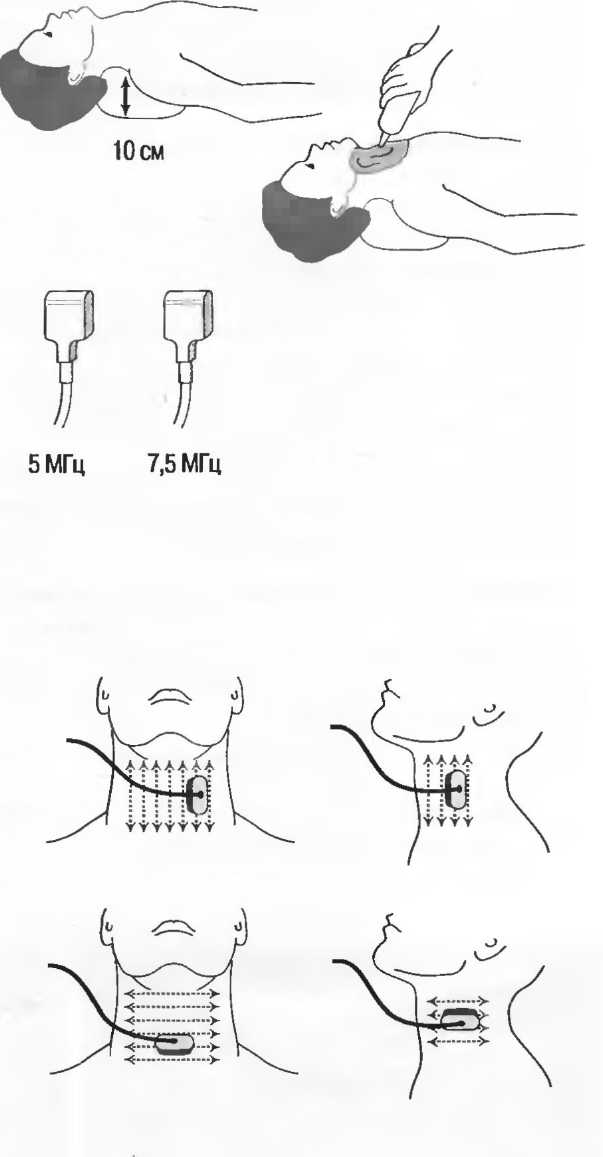

Наилучшим датчиком для общей практики является конвексный датчик с частотой 3,5 МГц с фокусировкой на расстоянии 7-9 см. Если такого датчика нет, необходимо наличие линейного секторного датчика с частотой 3,5 МГц. При необходимости исследования детей и худых взрослых желательно дополнить набор датчиком с частотой 5 МГц с фокусировкой 5-7 см.

1. Ультразвуковые исследования в акушерстве. Для общих исследований в акушерстве используется линейный или конвексный датчик с частотой 3,5 или 5 МГц с глубиной фокусировки на 7-9 см. Если закупается только один датчик, выбирайте датчик с частотой 3,5 МГц. Датчик с частотой 5 МГц предпочтителен на ранних сроках беременности. В поздние сроки беременности лучше использовать датчик с частотой 3,5 МГц.

2. Ультразвуковые исследования в общей практике. Если проводятся исследования в верхней части живота и таза у взрослых, в том числе и акушерские исследования, предпочтительнее выбор секторного или конвексного датчиков с частотой 3,5 МГц с глубиной фокусировки на 7-9 см.

3. Ультразвуковые исследования в педиатрии. Для детей необходим датчик с частотой 5 МГц с глубиной фокусировки на 5-7 см. При исследовании мозга новорожденного используется секторный датчик с частотой 7,5 МГц с глубиной фокусировки на 4-5 см (этот датчик также используется для исследования яичек и структур шеи у взрослых).